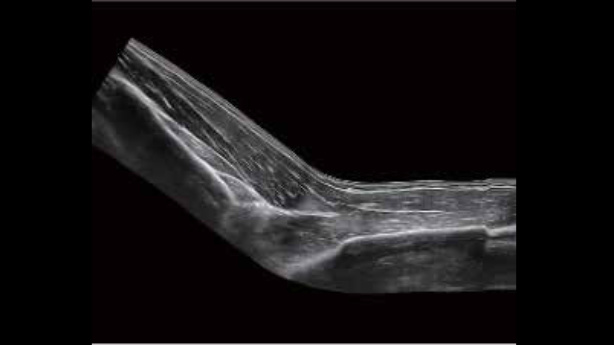

• zeus-fig5-2-1-uk

Kość ramienna w trybie B

• zeus-fig5-2-2-uk

Staw śródręczno-paliczkowy

Tryb panoramiczny iScape stawu łokciowego